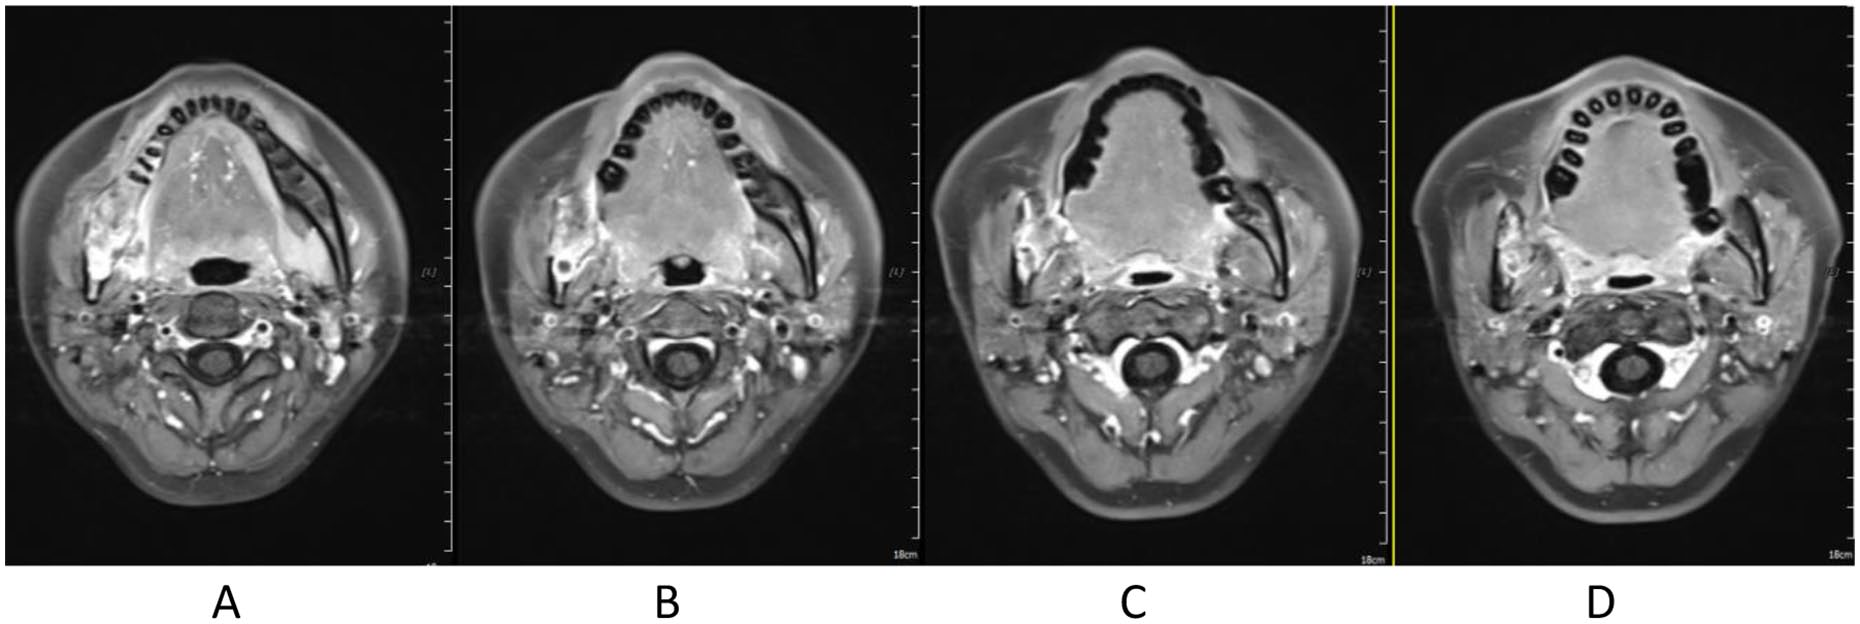

Treatment was tolerated well. During and after CIRT, there was only grade 2 skin (Figure 2) and oral mucosa acute adverse event, and no grade ⩾3 RTOG acute effect. During and after CIRT, her pain in the right mandible is continued but never aggravated, but painkiller is not needed; 6-month post completion of radiotherapy, she was in a very good clinical state, and the pain in the right mandible resolved completely. One to three months after CIRT, there were no significant changes of tumor size on MRI (Figures 3–6), just intensity of contract enhancement gradually diminished on contract-enhanced T1-weighted MRI; from 6months on, the size of the tumor decreased gradually (Figure 7); up to 16months after CIRT, it regressed to 3.6cm×3.2cm×1.7cm; and on 19months after CIRT, it regressed to 3.6cm×3.2cm×1.7cm, and the efficacy evaluation is PR (partial response) (Figures 8–10).

Figure 7. 6 months after CIRT.

Figure 8. 12 months after CIRT.